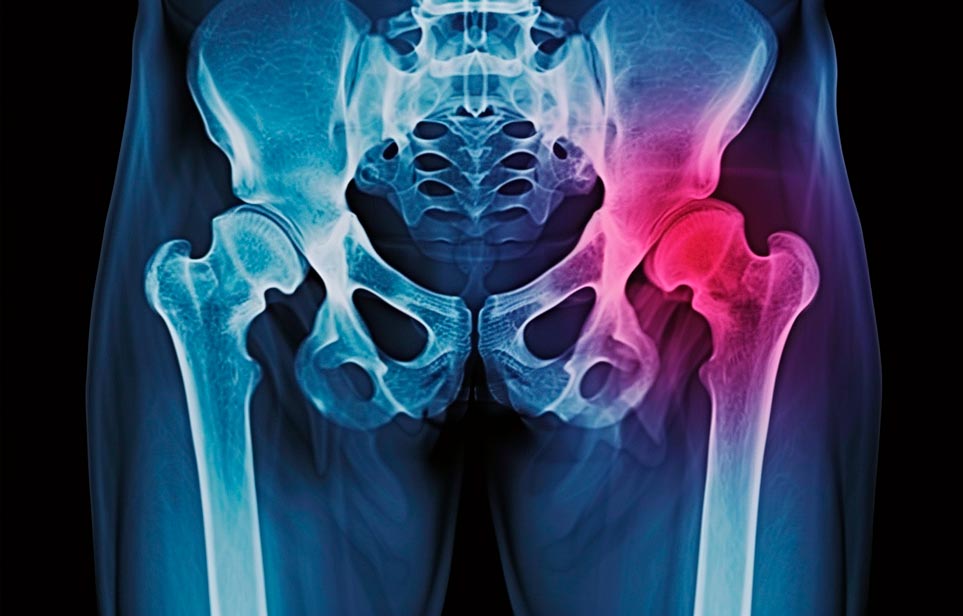

Реабилитация пожилых после перелома шейки бедра в Ялте

Эффективная и профессиональная реабилитация после перелома шейки бедра в Ялте осуществляется по демократичным ценам лучшими специалистами современной медицинской клиники «Заботливые люди» с применением персонального подхода к каждому пожилому человеку с такой тяжёлой травмой бедренной кости ноги. В процессе осуществления такой специализированной услуги все наши пациенты имеют возможность получения качественного и достойного обслуживания, эффективного восстановления. Лучший дом престарелых позаботиться о Вашем близком человеке.

Такая травма в большей части случаев возникает у граждан преклонного возраста. При её появлении на протяжении длительного времени сохраняются болевые и неприятные ощущения в области паха, при которых серьёзно ухудшается качество жизни, возникает множество последствий для его жизни и здоровья.

По какой симптоматике можно определить перелом шейки бедра?

Выявить его можно по возникновению следующей тревожной симптоматики:

- Визуально повреждённая нога сокращается на несколько сантиметром из-за сокращения мышц.

- Стопа выворачивается наружу.

- В лежачем положении человек не может поднять ногу.

При такой симптоматике важно незамедлительно обращаться к специалистам для получения всей необходимой помощи, терапии и восстановления после перелома шейки бедра. Если не оказать помощи старику, то это приведёт к гноению, инвалидности, иным видам осложнений.